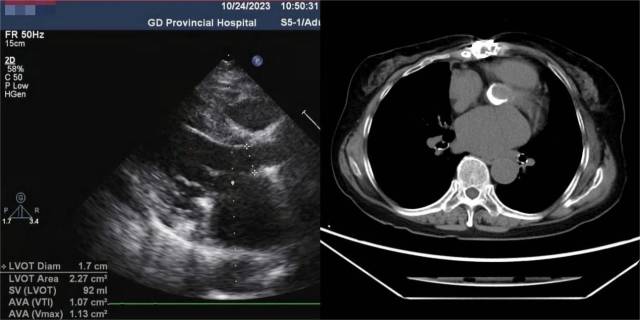

有感于陈女士求医的决心和充分的信任,治疗团队迎难而上,为其进行了详细的检查和手术策略评估。经食管超声心动图提示,患者主动脉瓣外侧瓣叶根部见强回声团,致瓣叶开放受限。CT图像可见主动脉瓣明显梗阻,二尖瓣钙化、腹腔干起始处重度钙化。

超声心动图、CT显示双瓣膜病变。 受访者供图